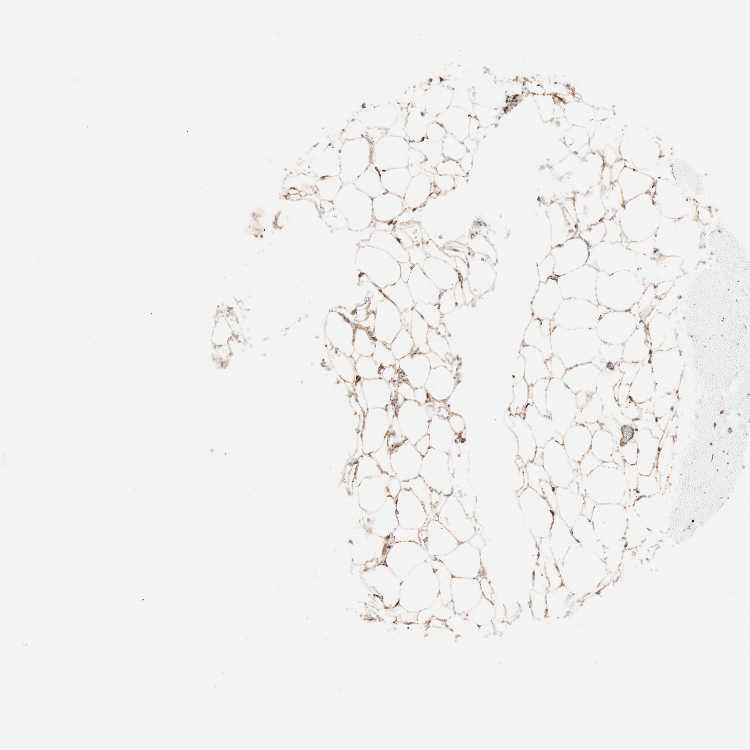

BREAST - Antibody stainingi

Antibody staining in the annotated cell types in the current human tissue is reported as not detected, low, medium, or high, based on conventional immunohistochemistry profiling in selected tissues. This score is based on the combination of the staining intensity and fraction of stained cells.

Each image is clickable and will lead to virtual microscopy that enables deeper exploration of all samples and also displays staining intensity scores, fraction scores and subcellular localization as well as patient and tissue information for each sample.

Antibody HPA069116Antibody CAB005429Antibody CAB039240Antibody CAB069907

Adipocytes HighMediumNot detectedMedium

Glandular cells HighHighMedium-